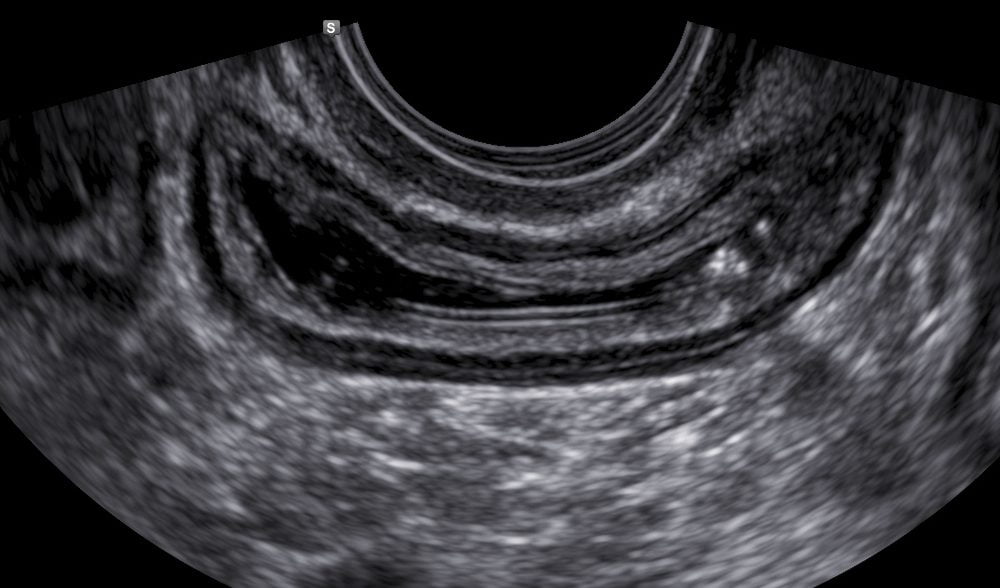

A via transvaginal diagnostica as lesões de endometriose mais comuns, como as localizadas na região retrocervical, ligamento uterossacro, intestino, vagina e bexiga.

- Septo retovaginal, reto e sigmoide;

- Região retrocervical e ligamentos uterossacros;.